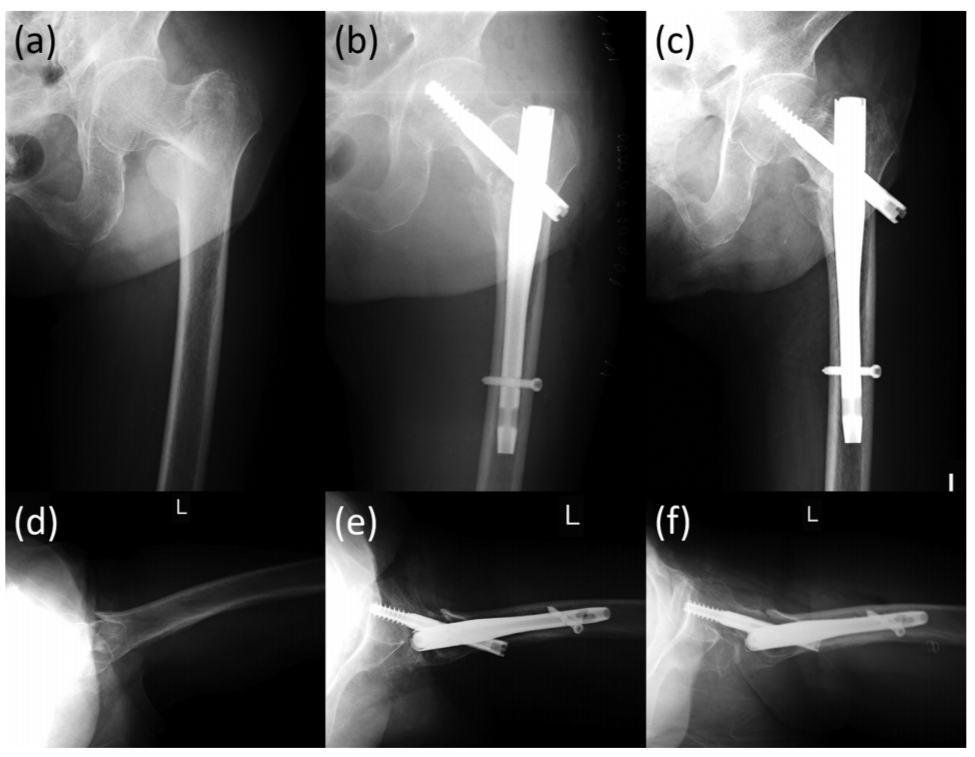

图4 一例89岁股骨粗隆间骨折患者,可见在正位片骨折显示良好,在侧位片上后区由于金属内植物遮挡,骨折部位显示不清。